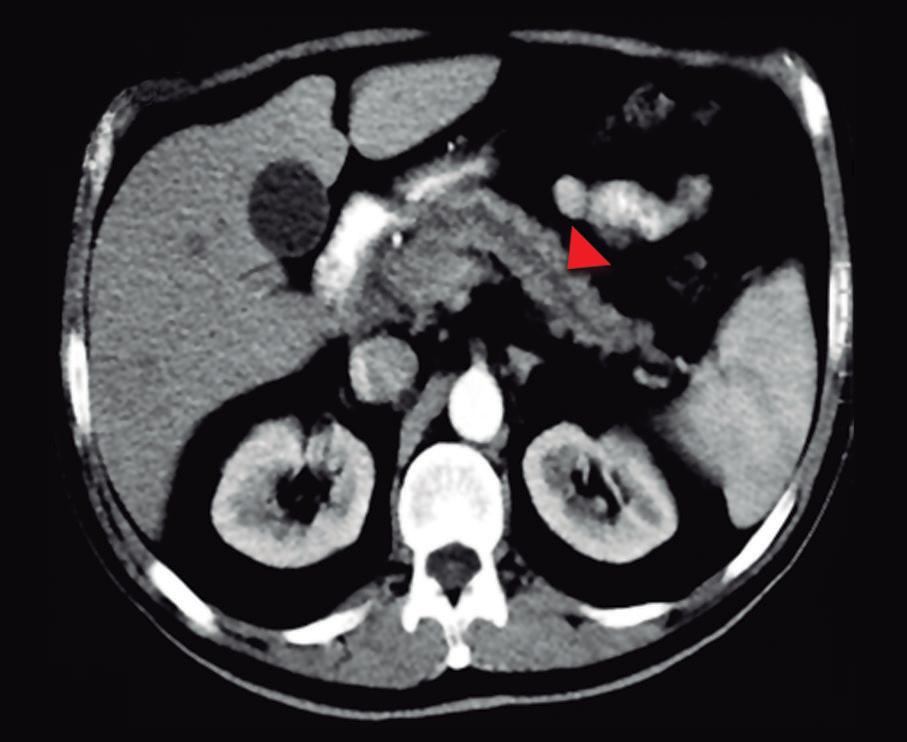

Paciente con vómitos en el periodo posoperatorio

Germán Francisco Rojas, Gabriel Adrián Mariño Camacho, Jesica Antonella Andruetto, Martín José Drago, Alejandro Moreira Grecco, Mariano Volpacchio, Esteban González Ballerga

Patient with Postoperative Vomiting